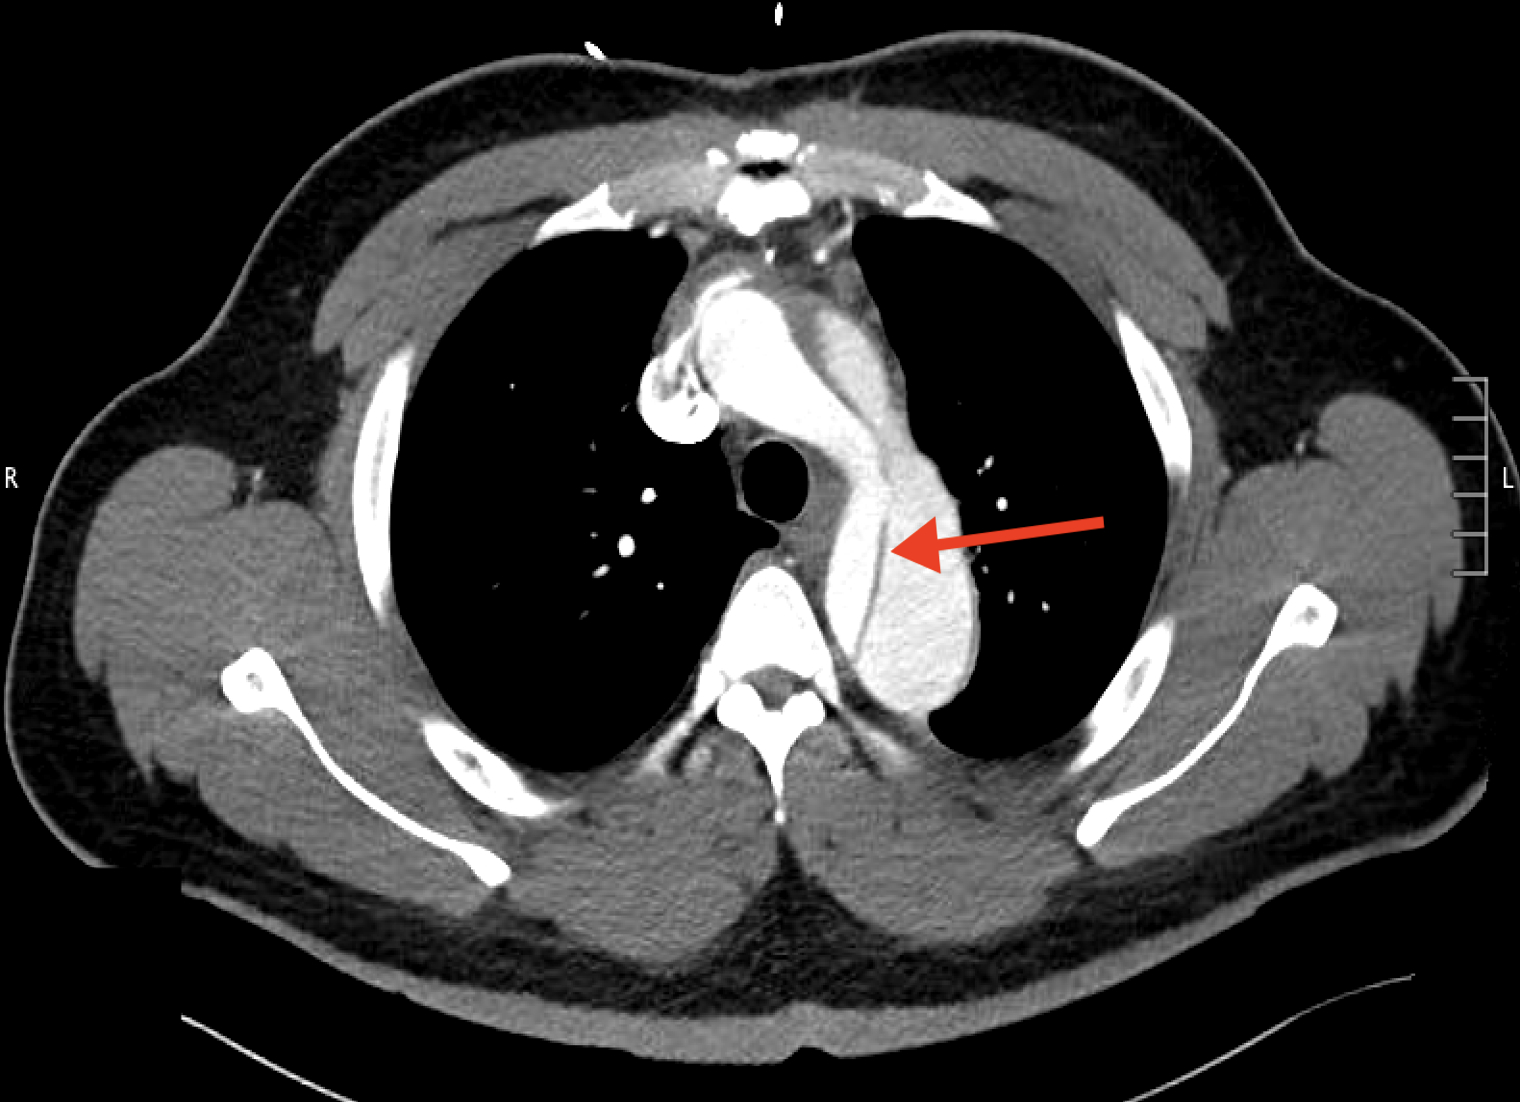

A 42-year-old male with history of a Type A aortic dissection with surgical repair 3 years earlier, resistant hypertension, hyperlipidemia, and prior tobacco use, presented for chest pain radiating to his back. Physical exam was notable for a 2/6 systolic murmur, most prominent at the aortic position. Initial vitals were significant for hypertension, with a blood pressure of 164/105 mmHg. Laboratory testing showed troponin elevated to 30 ng/L (reference < 15 ng/L), with a stable 3-hour trend. EKG showed normal sinus rhythm with left axis deviation and left ventricular hypertrophy. A CT angiography (CTA) dissection protocol showed a dissection flap distal to the left subclavian artery, extending into the abdominal aorta, consistent with a Stanford Type B aortic dissection (TBAD). The patient was managed with beta blockers and vasodilators to maintain systolic blood pressure under 120 mmHg and heart rate under 60 beats per minute. Following symptom resolution, a repeat thoracic CTA revealed a 2.5 cm sac near the origin of the right main coronary artery, representing a pseudoaneurysm not seen prior. Subsequent cardiac CTA confirmed this pseudoaneurysm outpouching secondary to degeneration of the TBAD. The patient underwent successful pseudoaneurysm repair with anastomosis construction and Dacron patch placement.

While the patient’s initial presentation and imaging studies, consistent with a TBAD, suggested conservative management, repeat imaging was imperative and changed the therapeutic plan despite the resolution of his symptoms. Current ACC/AHA guidelines recommend medical management for uncomplicated Type B dissections with close monitoring; however, aneurysmal progression mandates timely surgical intervention to mitigate rupture risk. This case highlights the importance of serial imaging in patients with TBADs to detect evolving complications such as APA formation, which may initially be occult but carry high mortality risk if left untreated.